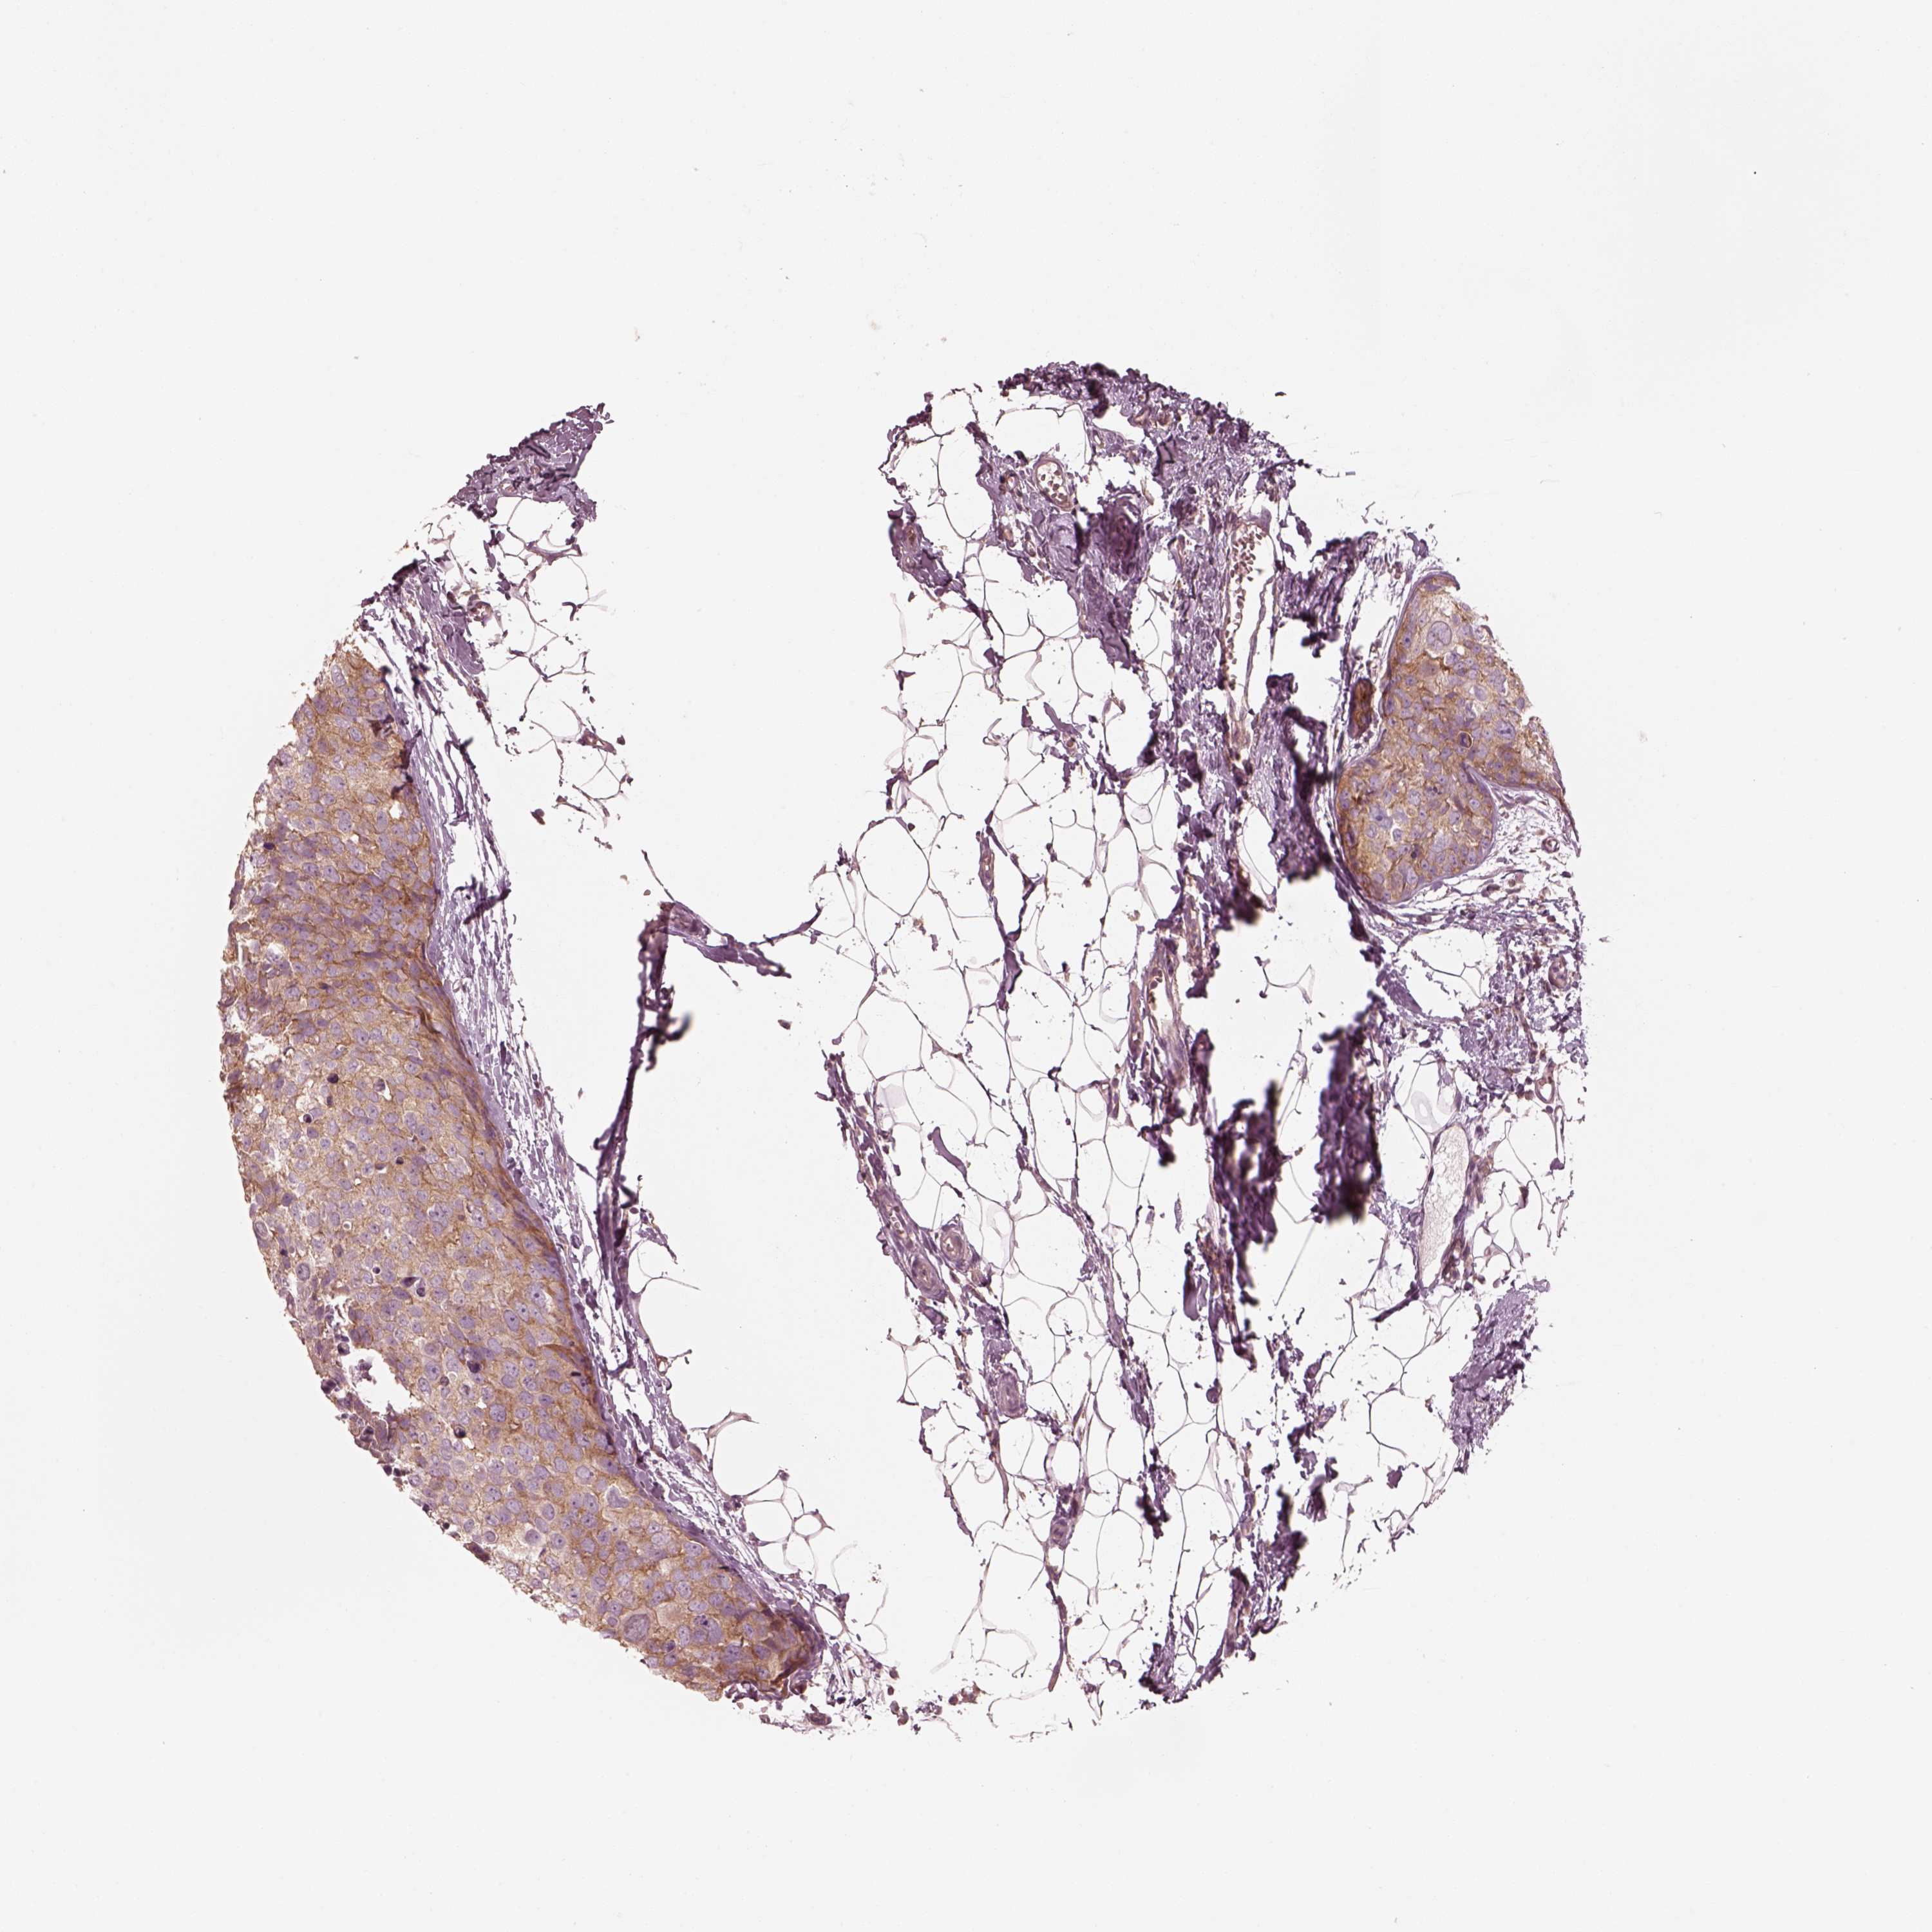

CANCER BREAST CANCER Show tissue menu

BRCA TCGA BRCA VALIDATION PROTEIN EXPRESSION